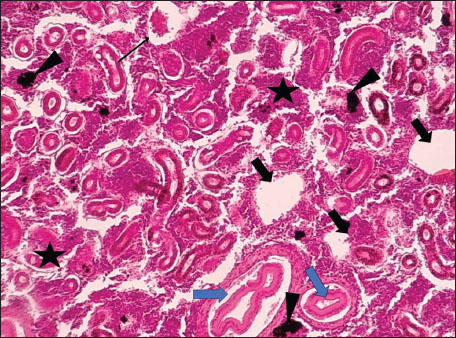

ABSTRACTBackground: The Mediterranean Sea has undergone significant ecological changes in recent decades, partly due to the introduction of non-native species. Lagocephalus sceleratus is an invasive Lessepsian species widely distributed in the Mediterranean, increasingly abundant along the Libyan coast, and potentially exposed to chronic environmental stressors. This species represents an important model for baseline pathological assessment in newly colonized marine environments. Aim: This study provides a descriptive histopathological assessment of kidney and gill tissues in adult L. sceleratus to document baseline tissue alterations without inferring direct environmental or pollution-related causation. Methods: A total of 150 adult specimens were collected from four Libyan coastal locations. Tissues were processed using standard histological techniques and evaluated semi-quantitatively (+, ++, +++) for lesion severity. Lesion severity grades were converted into ordinal numerical data and summarized using descriptive statistical approaches only. Results: Kidney tissues exhibited tubular degeneration, Bowman’s capsule dilatation, vascular congestion, extensive melanomacrophage centers (MMCs), and inflammatory lesions. Gill tissues showed disorganization of secondary lamellae, epithelial hyperplasia, edema, aneurysmal dilatations, vascular congestion, and MMC proliferation, some of which were associated with histologically observed parasitic structures. Conclusion: The observed alterations represent descriptive baseline tissue changes and should not be interpreted as direct evidence of pollution or specific environmental stressors. These findings provide reference data for future comparative pathological and ecological studies. Keywords: Lagocephalus sceleratus, Kidney, Gills, Histopathology, Melanomacrophage centers, Invasive species, Mediterranean Sea. IntroductionIn recent decades, the Mediterranean Sea has undergone profound ecological changes driven by the arrival and establishment of non-native marine species. Among these, Lagocephalus sceleratus has emerged as one of the most impactful Lessepsian migrants, due to its rapid geographic expansion, high ecological adaptability, and the presence of the potent neurotoxin tetrodotoxin in its tissues. This species has been widely documented to alter local fish communities, affect fisheries, and pose public health risks, making it an important target for biological and environmental assessment across the region (Katikou et al., 2022; Christidis et al., 2024). Fish are widely recognized as sensitive biological organisms in aquatic ecosystems, particularly in coastal habitats that are exposed to anthropogenic pressures such as industrial effluents, agricultural runoff, and untreated wastewater (Pinna et al., 2023). Among fish organs, the gills and kidneys are commonly regarded as sensitive to environmental stress, as they respond to physiological and pathological changes under environmentally suboptimal conditions. The gills, due to their large surface area and continuous exposure to surrounding water, are often the first tissues to exhibit structural alterations when fish encounter pollutants (Shahid et al., 2022). Histopathological changes in gills observed in polluted environments include epithelial lifting, lamellar fusion, hyperplasia, increased mucous cell density, and focal necrosis, which collectively reflect early physiological stress and potential compromise of respiratory function (Osman, 2010; Shahid et al., 2022). Similarly, the kidneys play crucial roles in osmoregulation, excretion of metabolic waste, and detoxification, making them highly vulnerable to chronic or systemic toxic effects (Wahidi et al., 2025). Documented renal lesions associated with chemical exposure include tubular deterioration, glomerular shrinkage, interstitial edema, and infiltration of inflammatory cells. These structural alterations often coincide with underlying biochemical disruptions, such as oxidative stress, impaired detoxification pathways, and activation of apoptotic mechanisms (Bernet et al., 1999; Authman, 2015). Despite the growing body of research on the ecological and toxicological implications of L. sceleratus, detailed histopathological assessments of this species remain scarce, especially in the southern Mediterranean basin, where environmental conditions and pollution profiles may differ from those in other regions. To date, detailed tissue-level studies of L. sceleratus from the southern Mediterranean are lacking, which limits the understanding of how this invasive species responds physiologically to local environmental stressors (Shakman et al., 2019; Ulman et al., 2021; Mohmmed et al., 2023). Accordingly, the present study aims to provide a comprehensive descriptive evaluation of histopathological changes in the kidneys and gills of L. sceleratus. The study is designed as a baseline histopathological assessment, focusing on tissue-level alterations without establishing causal links to environmental pollution or physicochemical stressors. By documenting structural aberrations and pathological features, this study contributes reference data for future monitoring and comparative studies in Mediterranean coastal ecosystems. Materials and MethodsSample designA total of 150 adult specimens of L. sceleratus, including both sexes, were collected from four Libyan coastal locations: Talamitha (n=39), Susah (n=34), Ain El-Ghazala (n=30), and Khalij Al-Bambah (n=47). Fish ranged in total length from 51 to 66 cm and in weight from 1.5 to 3.5 kg. Only apparently healthy adults were included, while juveniles were excluded to avoid age-related histopathological variation. Sampling was conducted opportunistically with assistance from local fishermen. All specimens were collected within a comparable seasonal window to minimize seasonal histopathological variability. Sex was recorded when possible; however, sex-based histopathological comparisons were not performed, as this was beyond the descriptive scope of the study. Fish were transported on ice at +4°C and examined in the Pathology Laboratory, Faculty of Veterinary Medicine, Omar Al-Mukhtar University (Mohmmed et al., 2023). Specimens were collected from a range of depths (0.5–70 m), with the majority from shallow waters (<10 m) and a subset (approximately 50 fish) from deeper locations (>30 m). Environmental physicochemical parameters such as temperature, salinity, and dissolved oxygen were not measured; therefore, no direct associations between histopathological findings and environmental variables were assessed. Tissue processing and histopathological examinationTissue specimens were fixed in 10% neutral buffered formalin for 24 hours. Following fixation, the samples were transferred to 70% ethanol for storage at room temperature. Subsequently, the tissues were processed for routine histopathological examination following standard procedures (Paul and Chanda, 2017). Paraffin embedding was performed, and 5 µm-thick sections were prepared using a microtome. Sections were stained with hematoxylin and eosin (H&E) and examined under a light microscope. Photomicrographs of representative lesions were captured using a high-resolution digital camera. Histopathological alterations were evaluated using a semi-quantitative scoring system adapted from Hose et al. (1996), Moshaie-Nezhad et al. (2021), and Alshailabi et al. (2023), where lesion severity was graded as mild (+), moderate (++), or severe (+++). Lesion severity grades (+, ++, +++) were converted into ordinal numerical values (1–3) for descriptive summarization of lesion severity. Due to the descriptive baseline nature of the study and the absence of a reference control group, inferential statistical comparisons were not emphasized or applied. Lesion severity scores were therefore summarized descriptively to avoid overinterpretation of the findings. Scoring was performed independently by two experienced observers, and representative lesions were confirmed across three sections per organ to ensure consistency. Tissues with visible parasitic structures were described separately from non-parasitized tissues to avoid conflating parasite-associated lesions with non-specific tissue alterations. The functional implications of the observed lesions were interpreted in accordance with Flores-Lopes and Thomaz (2011). Ethical approvalAll animal experiments conducted in this study were approved by the Ministry of Higher Education & Scientific Research and the Libyan National Committee for Biosafety & Bioethics, Libya. All procedures were performed in accordance with the relevant ethical guidelines, with session number 21/CH/25, dated 26/05/2021. ResultsHistopathological examination of the kidneyHistopathological examination of the kidney tissues of L. sceleratus revealed multiple alterations. Prominent melanomacrophage centers (MMCs), necrotic areas, dilatation of Bowman’s capsules, and vacuolar degeneration were observed (Fig. 1), associated with interstitial lymphohematopoietic tissue (Fig. 2). Dilated and congested blood vessels and extensive MMCs were also noted (Fig. 3). Renal degeneration surrounding lymphohematopoietic tissue, large clusters of MMCs, and thickened, congested vessel walls within fibrotic areas were evident (Fig. 4). Atrophic renal degeneration with necrotic and vacuolar changes was observed (Fig. 5). Severe inflammatory infiltration of lymphatic cells and granulomas with necrotic centers, surrounded by fibrous tissue, was detected (Figs. 6–7).

Fig. 1. Histopathology of the kidney in an adult L. sceleratus showing kidney parenchyma (stars), MMCs (head arrows), necrotic tissue (thick arrows), dilatation of Bowman’s capsule (thin arrow), and vacuolar degeneration (blue arrows). ×100 H&E.